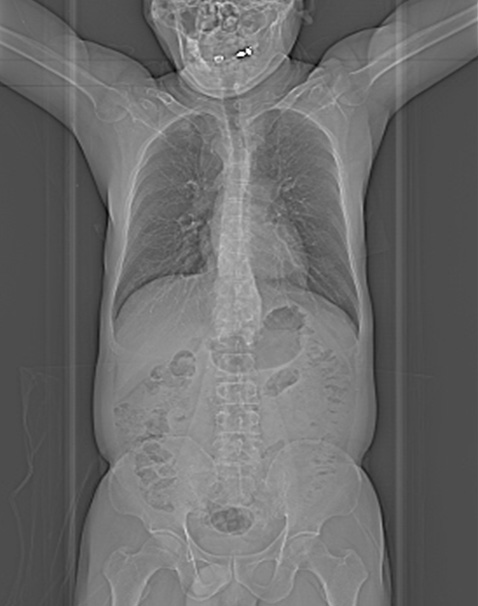

cardiomegaly on x-ray 11/F

Kyungsun Nam, Department of Radiology, Yonsei University College of Medicine